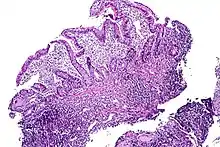

| Tissue of the ileum with inflammatory changes due to Crohn's disease | |